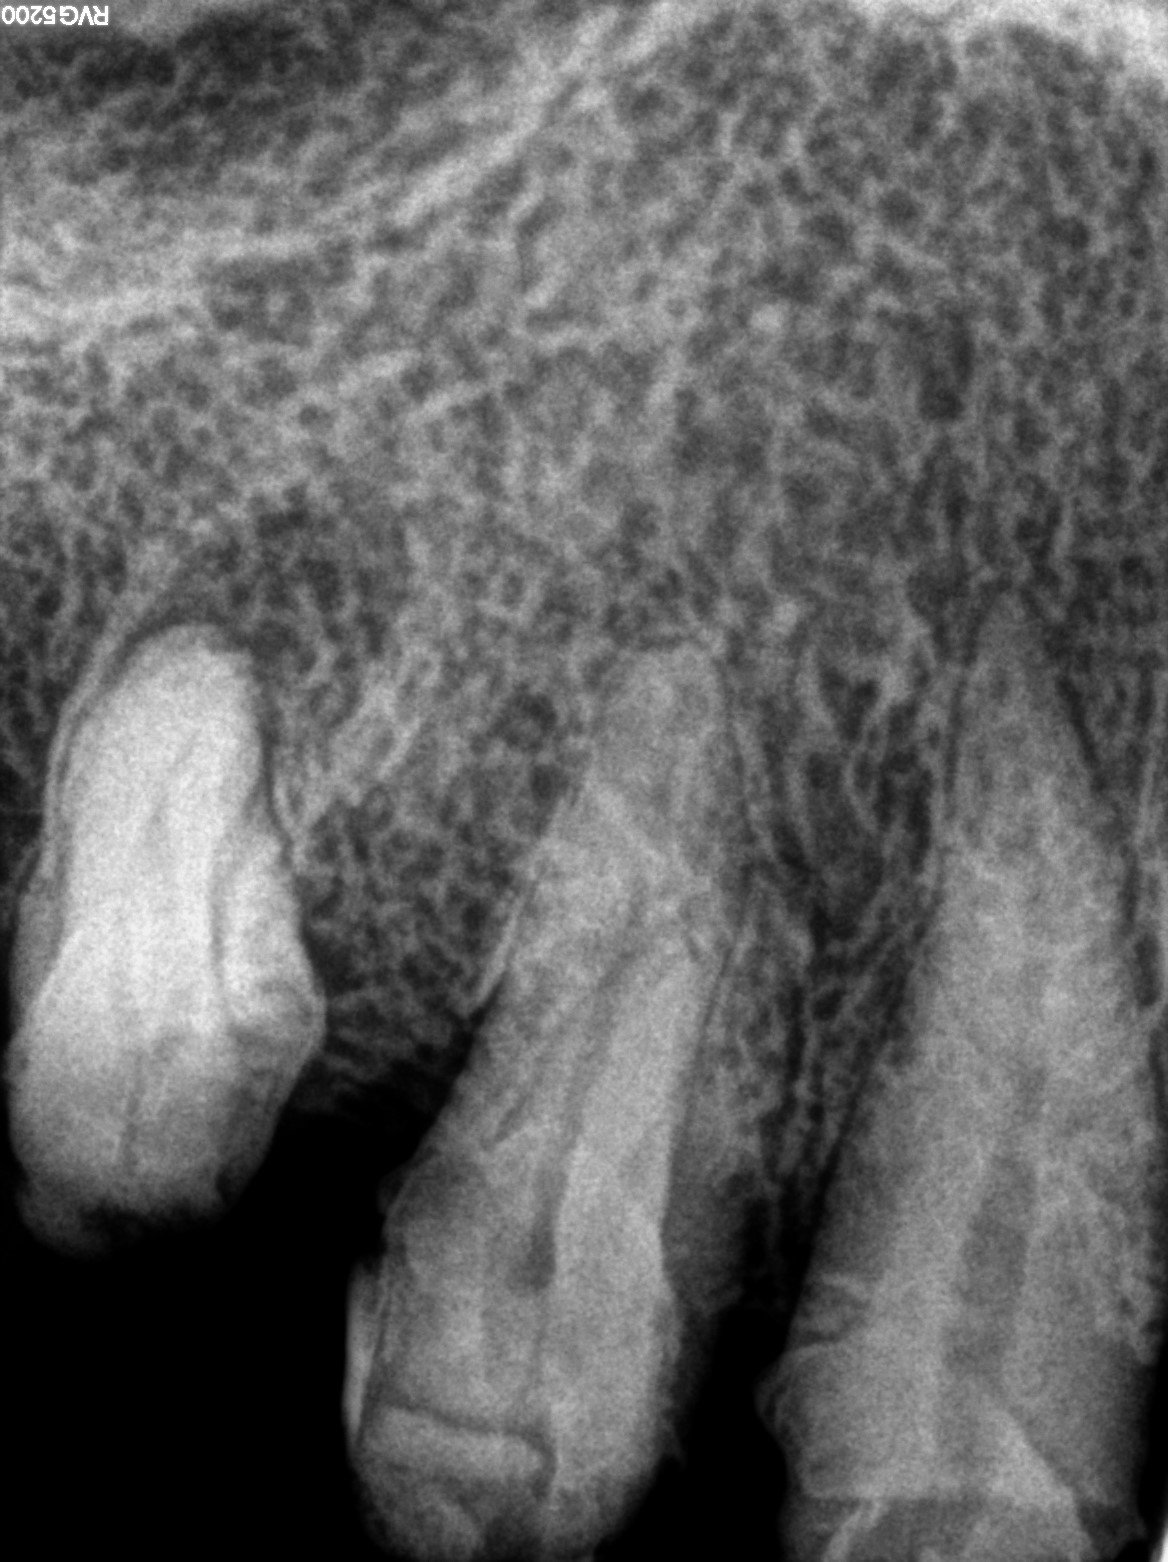

Dental Radiographs FHIR: DocumentReference · LOINC 24641-7

R71.jpg

24641-7

R73.jpg